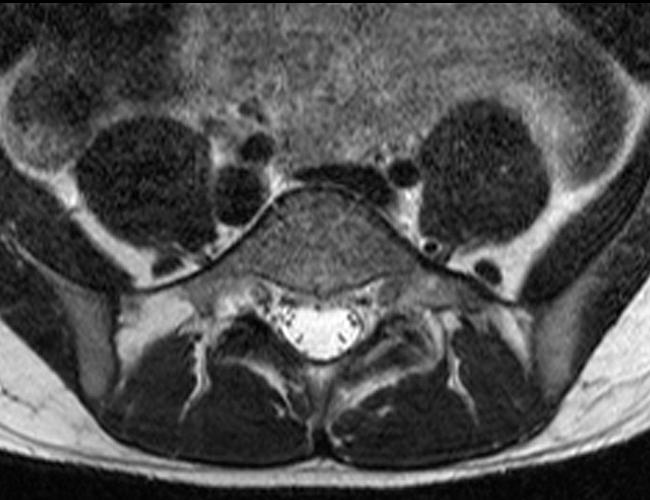

Case 2: 19-year-old male baseball player with acute onset of back pain after hitting a ball. Axial T1-weighted (2A) and T2-weighted (2B) images are provided. What are the findings? What is your diagnosis?

Case 2: T1-weighted (4A) and T2-weighted (4B) axial images show T1 hypointensity and T2 hyperintensity (arrowheads) in the left lamina of L5 adjacent to a small hypointense line (arrows) which traverses the lamina.

Case 2: Acute left-sided laminolysis